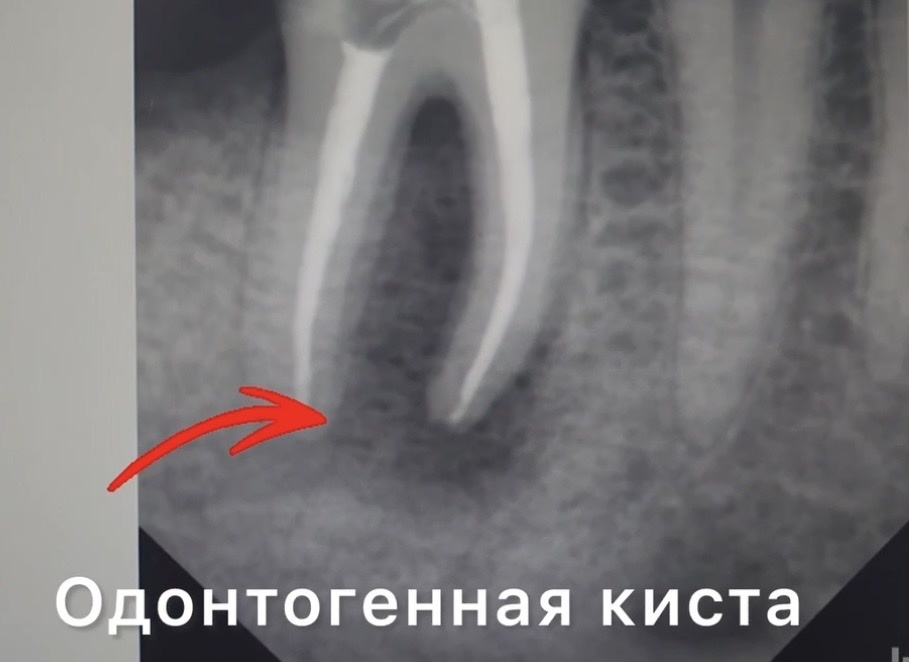

Консервативное лечение одонтогенных кист челюсти

Консервативное лечение одонтогенных кист челюсти - это современный и щадящий подход, который часто позволяет сохранить зуб и избежать хирургического вмешательства. Такой метод особенно эффективен при небольших кистах и ранних стадиях заболевания. В основе консервативного лечения лежит эндодонтическая терапия: врач вскрывает канал «причинного зуба», удаляет инфицированные ткани, промывает канал антисептиками и закладывает лекарственные препараты. После стабилизации состояния и полной санации канал герметично пломбируется, а пациенту назначают дальнейшее наблюдение для контроля за состоянием (периодическую рентгенографию). В отдельных случаях консервативная терапия дополняется курсом антибиотиков и противовоспалительных средств. Такой подход помогает добиться рассасывания небольших кист с сохранением зуба, но требует строгого соблюдения рекомендаций специалиста и регулярного контроля! Преимущества консервативного лечения - это конечно же сохранение своего зуба и минимальное врачебное вме